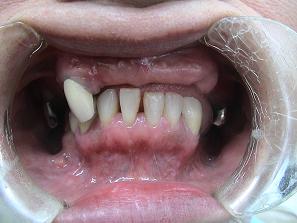

【症例 2】 11歯欠損 (51才,女性)

正面上(ミラー像)下(ミラー像)

1.

術前のお口の状態です